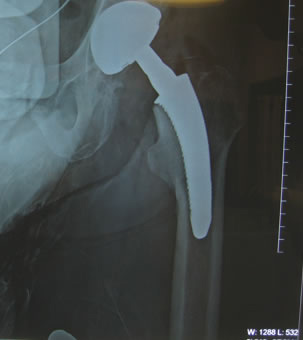

| Apex Modular Stem was used that features a special “Dual Press” modular junction. This design allows for selection of a variety of femoral offsets and one of three version angles: Neutral or 13º of anteversion or retroversion. |

| Pre-operative consideration was discussed on shorting the stem to avoid any potential femoral canal perforations. For this reason a special proximal modular stem “Dual-Press” design was utilized. Proximal conical reaming was done without the use of a pilot shaft along with rasping of the femoral triangle. |

| The stem fit was excellent with impressive implant to bone stability. The proximal modular neck design allowed selection of a variety of femoral offsets and neck lengths. This along with large head M-O-M (40mm) bearings provided significant ROM and hip joint stability. The short stem functions as a pilot with implant to bone stability provided by proximal stem geometry (cone & triangle). |

Modular necks allows for neutral or 13º of anteversion or retroversion. In this case the head-neck was retroverted for best joint stability position. Target Restoration was established. |

| You will notice when you take out the pelvic obliquity it is 45 degrees |